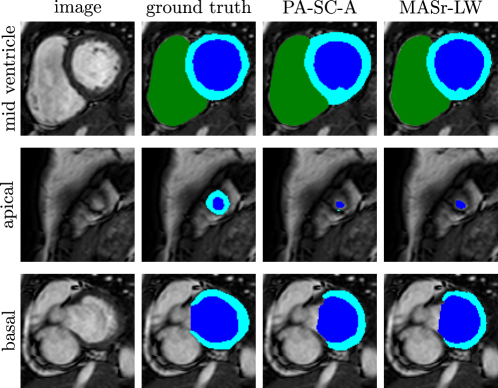

Figure 12(a) shows mean Dice coefficients for the first group of experiments, where scribbles were placed on the atlases, and completely unlabelled target images were segmented using the proposed framework. It can be seen that using scribbled atlases (PA-SC-A) yielded results comparable to MASr-LW (where fully annotated atlases were used) for the right and left ventricle. For the myocardium, using scribbled atlases could not match the accuracy achieved when using fully annotated atlases. Figure 13 shows example segmentation results for one subject. It can be seen that the results of PA-SC-A and MASr-LW are similar. However, since there is no boundary delineation in the scribbled atlases, the resulting segmentation results for PA-SC-A were more intensity driven as can be seen for example in the myocardium in the mid-ventricular view.

The results for the second group of experiments are shown in Fig. 12(b). Here, the target images to be segmented contained scribbles. In the simplest configuration PA-SC-T, a target segmentation is obtained from the scribbled target image only. Adding the scribbled atlases (PA-SC-A+T) yielded results very similar to PA-SC-T. However, placing scribbles in a target image to aid segmentation using fully annotated atlases (PA-SC-AF+T) yielded considerable improvements over both PA-SC-T (as seen in Fig. 12(b)) and MASr-LW (as seen in Fig. 12(a). Visual results for these experiments are shown in Fig. 14 for the same subject as above. It can be seen that all three methods containing target scribbles were able to detect the myocardium in the apical slice, which was not possible using only atlas information (as seen in the middle row in Fig. 13). Furthermore, it can be seen that the segmentation obtained with fully annotated atlases and a scribbled target image (PA-SC-AF+T) is visually very similar to the ground truth segmentation, which is also reflected in the high Dice scores reported in Fig. 12(b).

4.4 Analysis of Parameter Sensitivity